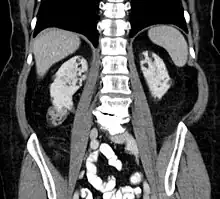

Kidneys

Between 60 and 80% of TSC patients have benign tumors (once thought hamartomatous, but now considered true neoplasms) of the kidneys called angiomyolipomas frequently causing hematuria. These tumors are composed of vascular (angio–), smooth muscle (–myo–), and fat (–lip-) tissue. Although benign, an angiomyolipoma larger than 4 cm is at risk for a potentially catastrophic hemorrhage either spontaneously or with minimal trauma.

- Repeat MRI of abdomen every one to three years throughout life. Check renal (kidney) function annually. Should angiomyolipoma bleed, this is best treated with embolisation and then corticosteroids. Removal of the kidney (nephrectomy) is strongly to be avoided. An asymptomatic angiomyolipoma that is growing larger than 3 cm is best treated with an mTOR inhibitor drug. Other renal complications spotted by imaging include polycystic kidney disease and renal cell carcinoma.